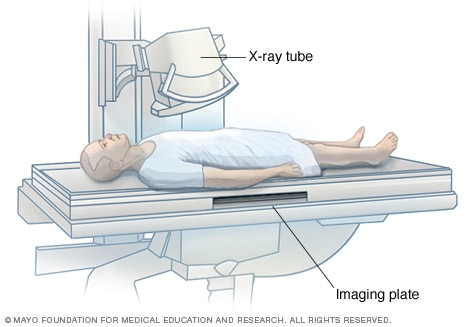

X-ray exam

The X-ray tube is focused on the abdomen. X-rays will pass through the body and produce an image on the specialized plate below.

X-rays are performed at medical offices, dentists' offices, emergency rooms and hospitals — wherever an X-ray machine is available. The machine produces a safe level of radiation that passes through the body and records an image on a specialized plate. You can't feel an X-ray.

A technologist positions your body to get the necessary views. Pillows or sandbags may be used to help you hold the position. During the X-ray exposure, you remain still and sometimes hold your breath to avoid moving so that the image doesn't blur.